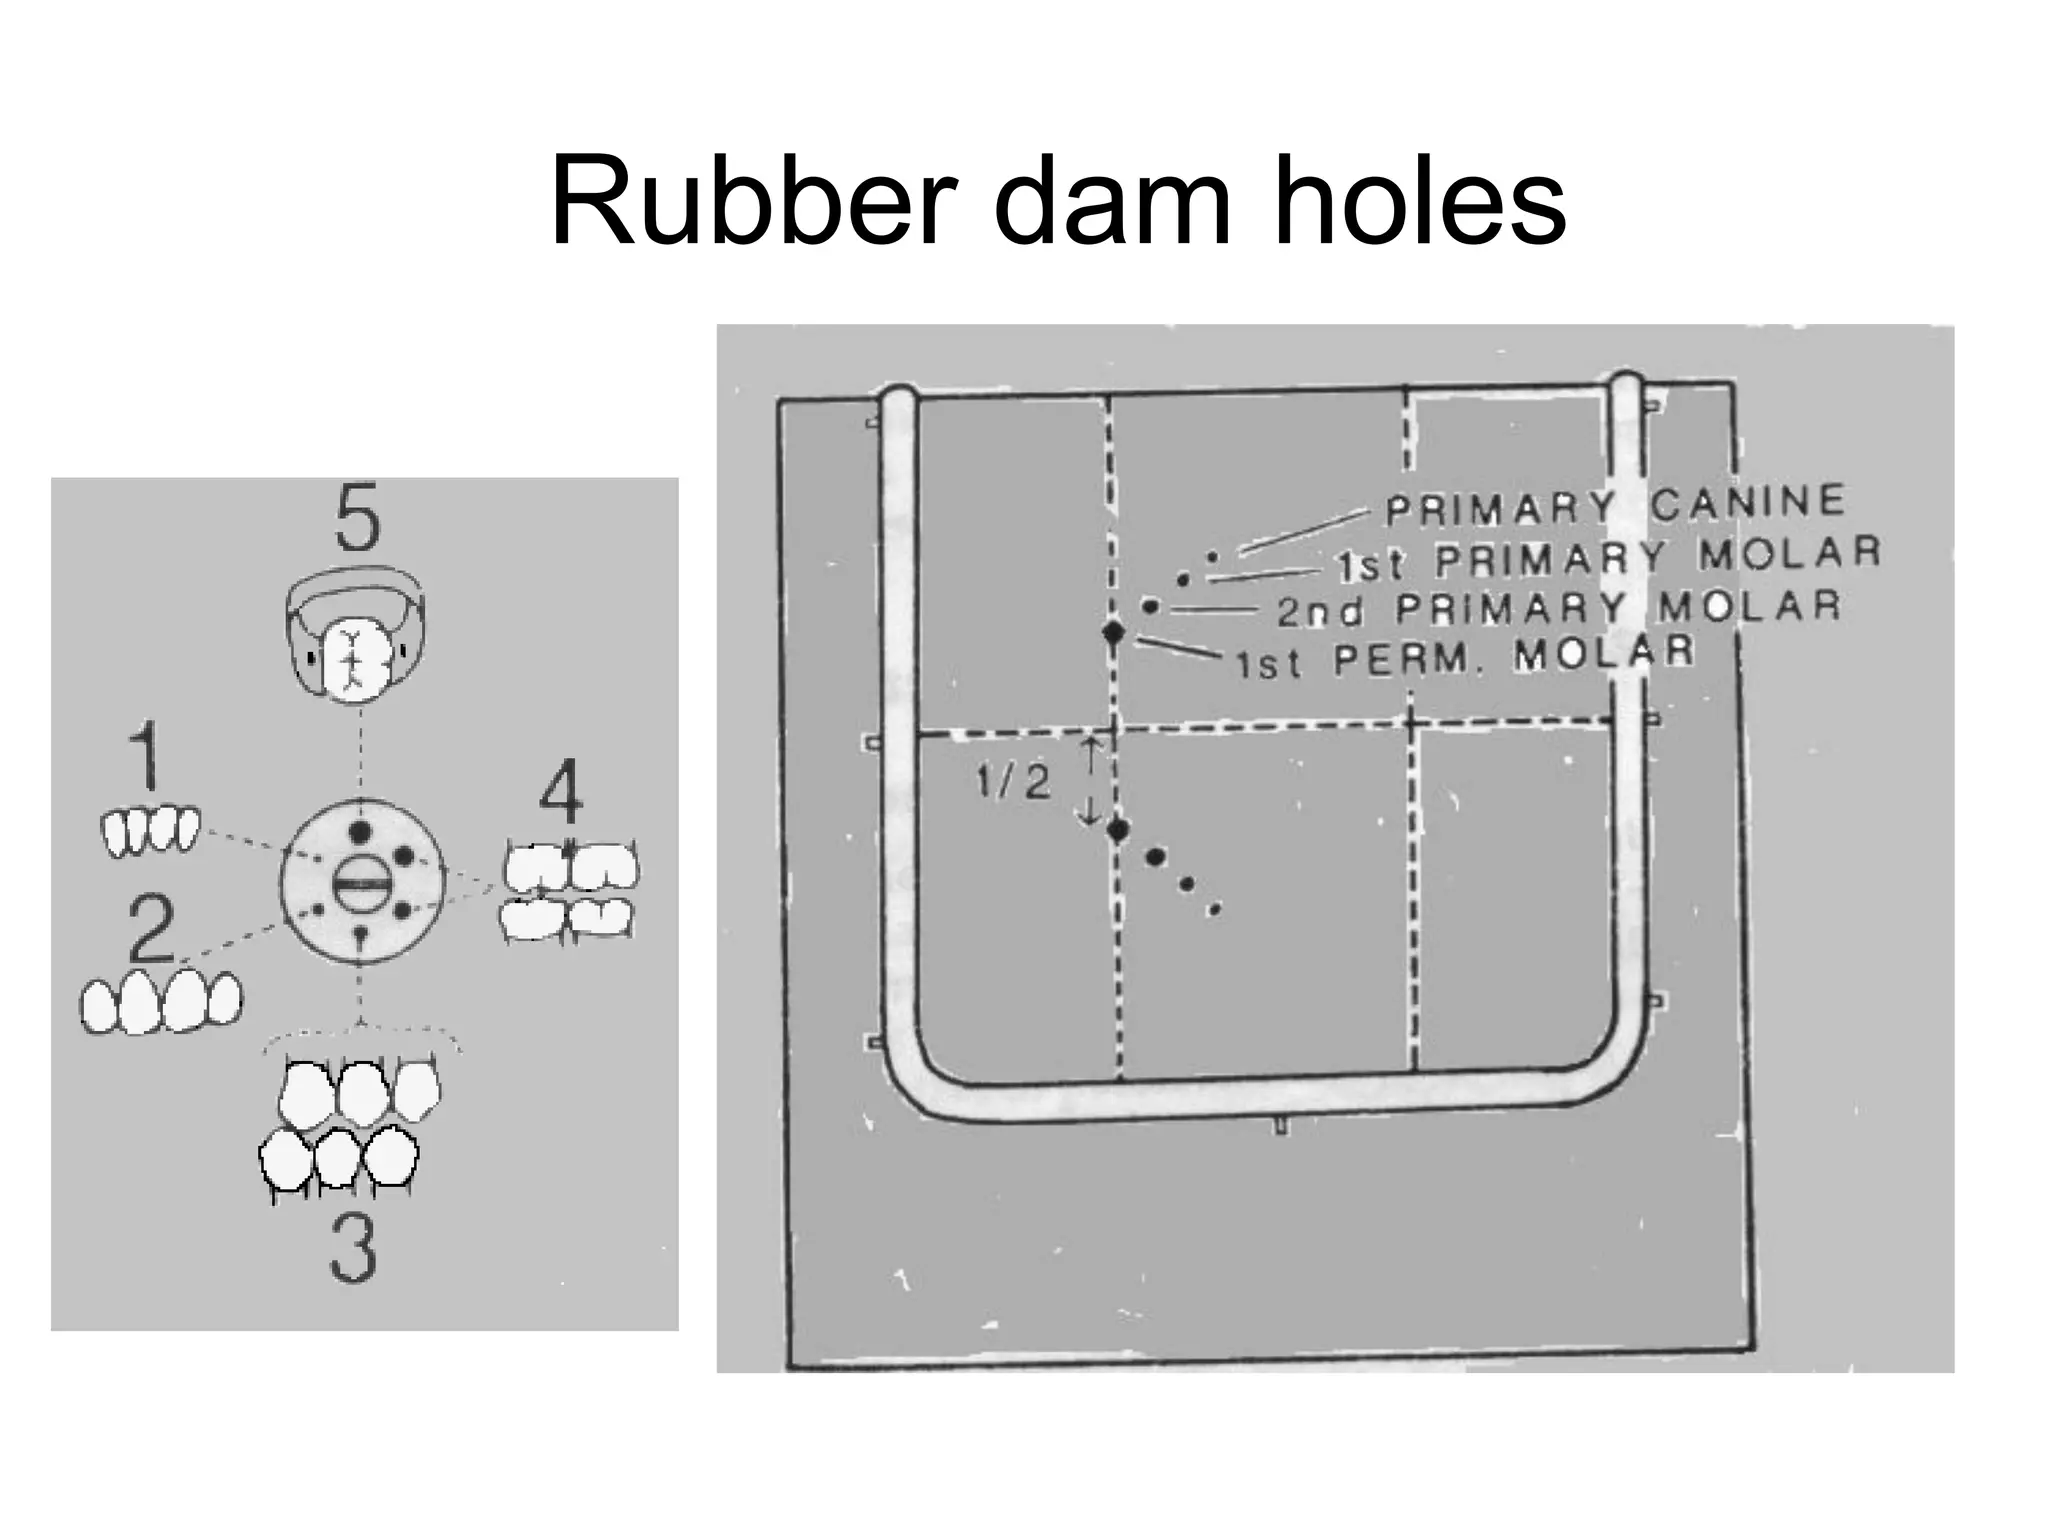

This document discusses the materials and components used for rubber dam isolation in dentistry. It describes the different types of rubber dam materials including color options and napkins to absorb moisture. It also outlines the tools needed such as punches to make holes, templates and stamps to guide hole placement, clamps to secure the dam, and other accessories like wedges and lubricant. Finally, it provides guidance on punching holes for different types of teeth and properly placing clamps in the rubber dam.